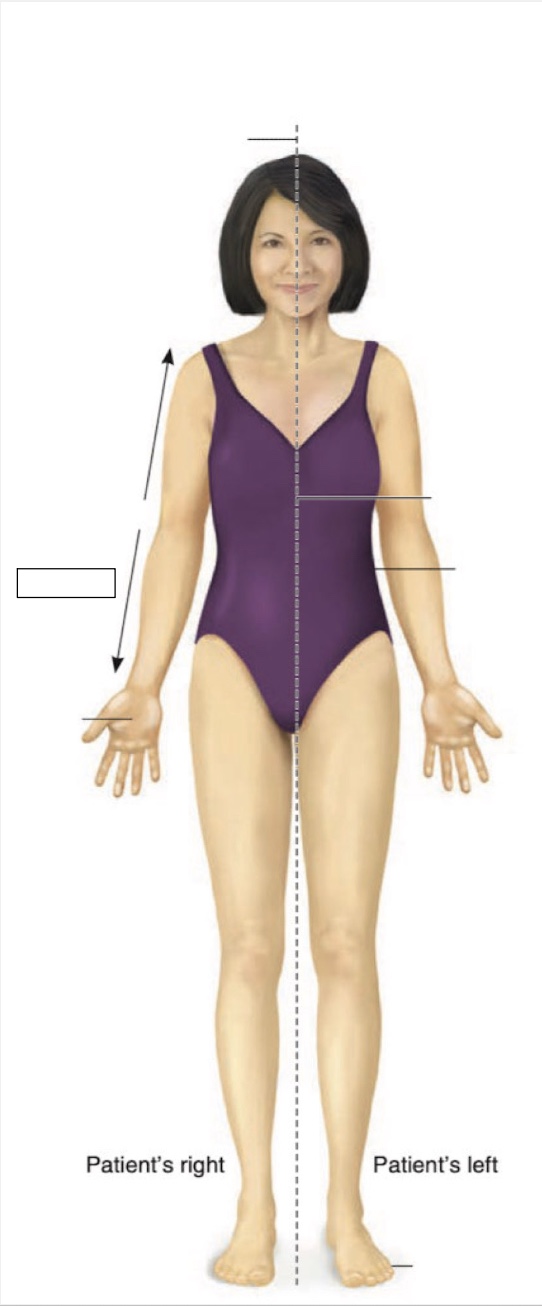

Posterior

Anterior

Superior

Inferior

Midline

Proximal

Distal

Palmar

Medial

Lateral